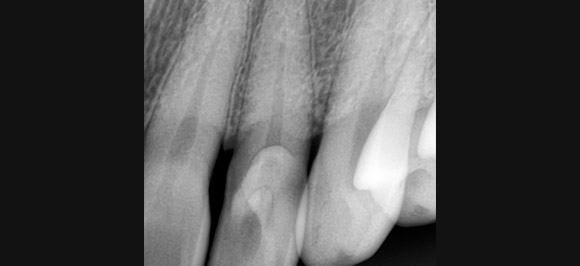

신경(근관)치료

평생에 한번 뿐인 소중한 내 자연치아를 보존!

염증으로 인해 치아 깊숙한 곳까지 번져 통증을 유발

감염된 신경을 제거하고 멸균한 후, 내부와 외부를 보호

내 자연치아를 살리는 마지막 수단!